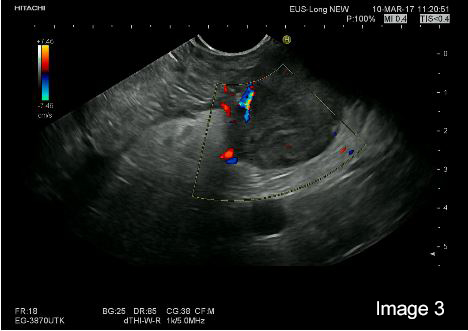

EUS was performed with a Pentax E-3870 UTK linear echoendoscope and Hitachi Ascendus scanner. On B-mode EUS the tumour in the head and tail appeared very similar with a generally hypoechoic inhomogeneous echogenicity pattern and apparently small cystic areas within otherwise solid tumours. Also, the two smaller lesions could be identified in the body and tail of the pancreas. We concentrated the further examination on the lesion in the tail of the pancreas, with a diameter of 25 mm (Image 1 and 2).

On strain based elastography, the tumour tissue was repeatedly imaged as harder than the surrounding pancreatic parenchyma (Image 1 and 2).

Image 2: The hypoechoic tumor tissue in the B mode image is repeatedly corresponding to the blue area indicating harder tissue in the elastogram (left)